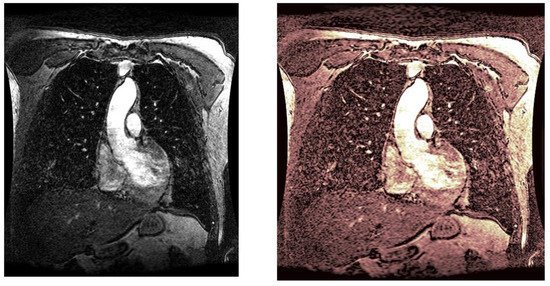

As statistical data have less relevance for life sciences, we add graphical displays of the studied angiograms. Surprisingly, even a simple denoising procedure can help reduce unwanted artifacts, as can be observed when comparing the angiogram E1154S7I064 (shown in Figure 5) with the result obtained by denoising it with the CLAHE method already described (shown in Figure 6). The corresponding image obtained by the wavelet-based CE method (shown in Figure 7) better outlines the biological features, making visible some details that cannot be observed in the original image (Figure 5), and allows us to take into consideration relinquishing contrast substances (a fact with multiple benefits for newborns and children). A visual comparison of CLAHE and wavelet-based CE method results in the performance obtained for this angiogram can be made with the images in Figure 8. It can be noticed that the original image is too dark to observe all the significant medical details and that the result of CLAHE is too luminous and can mask medical features. The same remarks concerning the advantages of the wavelet-based CE methods can be made upon a visual analysis of the original angiograms and the corresponding results shown in Figure 9, Figure 10, Figure 11 and Figure 12.

Figure 12. Original angiogram E1154S7I075 (left) and wavelet-based CE method result (right).